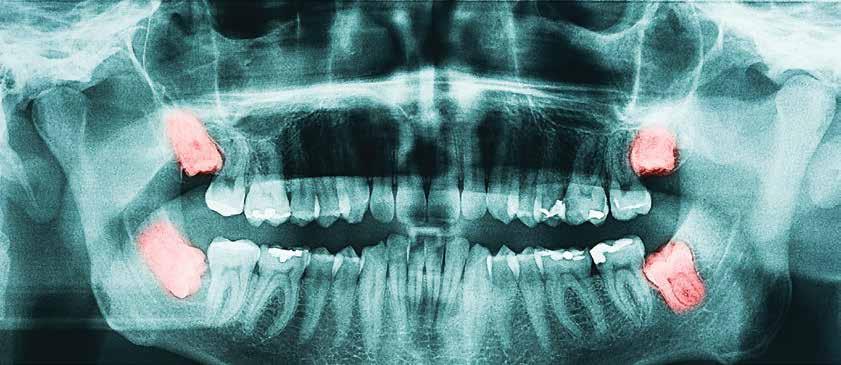

[Healthy Life] If you’ve got them, why remove them? Wisdom teeth (third molars) are in the very back of your mouth. Sometimes, these molars remain under the gums and never come in. Wisdom teeth that do not come in or do not have room to erupt completely are termed “impacted.” If you are unsure if you have impacted wisdom teeth, your dentist can make this determination.

Although you may not currently have any pain or issues with your wisdom teeth, that does not mean you won’t ever have problems. In some cases, tumors can grow around impacted wisdom teeth, destroying the jawbone. By extracting them, you remove this possibility.

Often, partially erupted wisdom teeth cause “gum pain” or significantly contribute to periodontitis, a common and serious disease that causes the supporting bone around the tooth to deteriorate. Once the bone deteriorates, the tooth becomes loose and eventually falls out.

Unfortunately, destroyed jawbone does not grow back. Periodontitis around wisdom teeth spreads to neighboring teeth, causing additional bone loss around otherwise healthy molars. An astute dentist will recognize this nearly inevitable condition and can guide you through the appropriate treatment for preventing this incurable disease. By removing your wisdom teeth, you can better clean your other molars in the back of your mouth, which can also help prevent periodontitis.

Should everyone get their wisdom teeth removed? Discuss this question with your dentist. It depends upon a thorough examination and your individual situation. It also depends upon the oral health risks you are willing to live with. A patient’s age and health history should always be a consideration. Also, even though your wisdom teeth might not bother you right now, you should consider having them removed to prevent future issues.

Removal of wisdom teeth is a common and generally safe surgery with very few risks. Many general dentists remove wisdom teeth safely and efficiently using local anesthesia. Oral surgeons usually use anesthesia that puts you to sleep for the procedure. As with any surgery, complications can arise. Most complications are successfully managed, and patients usually heal quickly.

Remember, early prevention is a key principle in dentistry, and accepting preventative dental treatment often makes a big difference later in life. After all, great dentistry focuses on you, even if it means removing a wisdom tooth. L